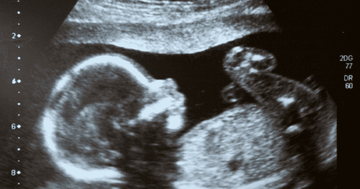

During the first trimester, it can sometimes be difficult to know whether a pregnancy is viable. In early pregnancy, ultrasound scans are used to assess development, but occasionally it may take more than one scan to confirm the outcome.

At this scan, your doctor will check that your baby is developing as expected for how far along you are, and that the pregnancy is located safely in the uterus (not the fallopian tubes). The ultrasound also helps detect any early developmental concerns for you or your baby. This first scan is often called a dating scan because it helps confirm how far along you are and estimate your due date. It’s usually done around 6 to 8 weeks of pregnancy, and the earlier it’s performed, the more accurate it tends to be.

Seeing your baby’s heartbeat for the first time is a wonderful moment, it confirms that the pregnancy is viable and progressing as it should. The tiny heart usually starts beating about 22 to 25 days after conception, but it’s typically visible on ultrasound from around 6 weeks.